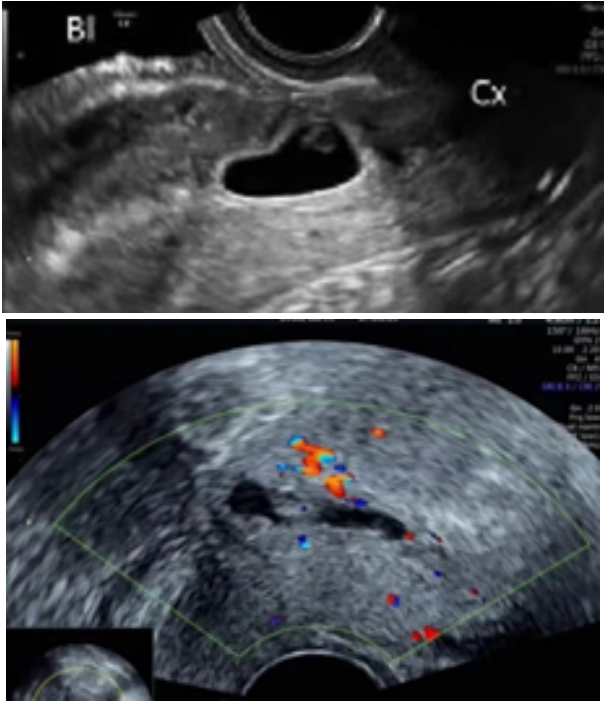

🔹II型

• 妊娠囊与膀胱间子宫肌层厚度≤3mm;

• 此型囊胚着床于缺损瘢痕的裂缺内。